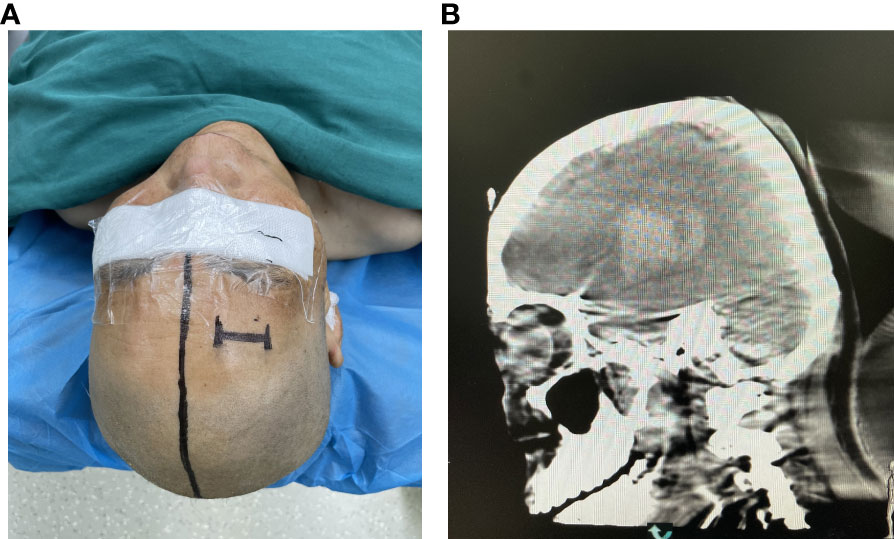

The surgical incision site was marked with a metal object on the forehead, approximately 2 cm from the midline and 3 cm from the orbit on the hematoma side (Figure 2). The priority was to make an incision in the frontal stria and avoid the frontal sinus to prevent cerebrospinal fluid leakage after surgery and ensure an aesthetically pleasing appearance after wound healing. A hole was drilled in the bone at the metal mark (Figure 3). The C-arm CT function of the digital subtraction angiography (DSA) machine was used to collect the original data for processing; display the coronal, sagittal, and axial CT images; mark the center of the hematoma; and set it as the target site for the puncture (Figure 4). The 3D reconstruction of brain tissue was performed using the 3D reconstruction software Xper CT of the DSA machine, and the bone hole displayed in gray scale was adjusted as the puncture point. Subsequently, the 3D stereo image was rotated, overlapping the puncture point and puncture target. The laser emission direction was determined using the principle of “two points and one line,” and the real-time 3D reference image working angle was recorded (Figure 5). The skull was cut along the coinciding point, and the distance between the puncture point and the puncture target was measured as the puncture depth (Figure 6).

Figure 2 (A) The percutaneous puncture point was marked. (B) Confirming the puncture point in the CT image.